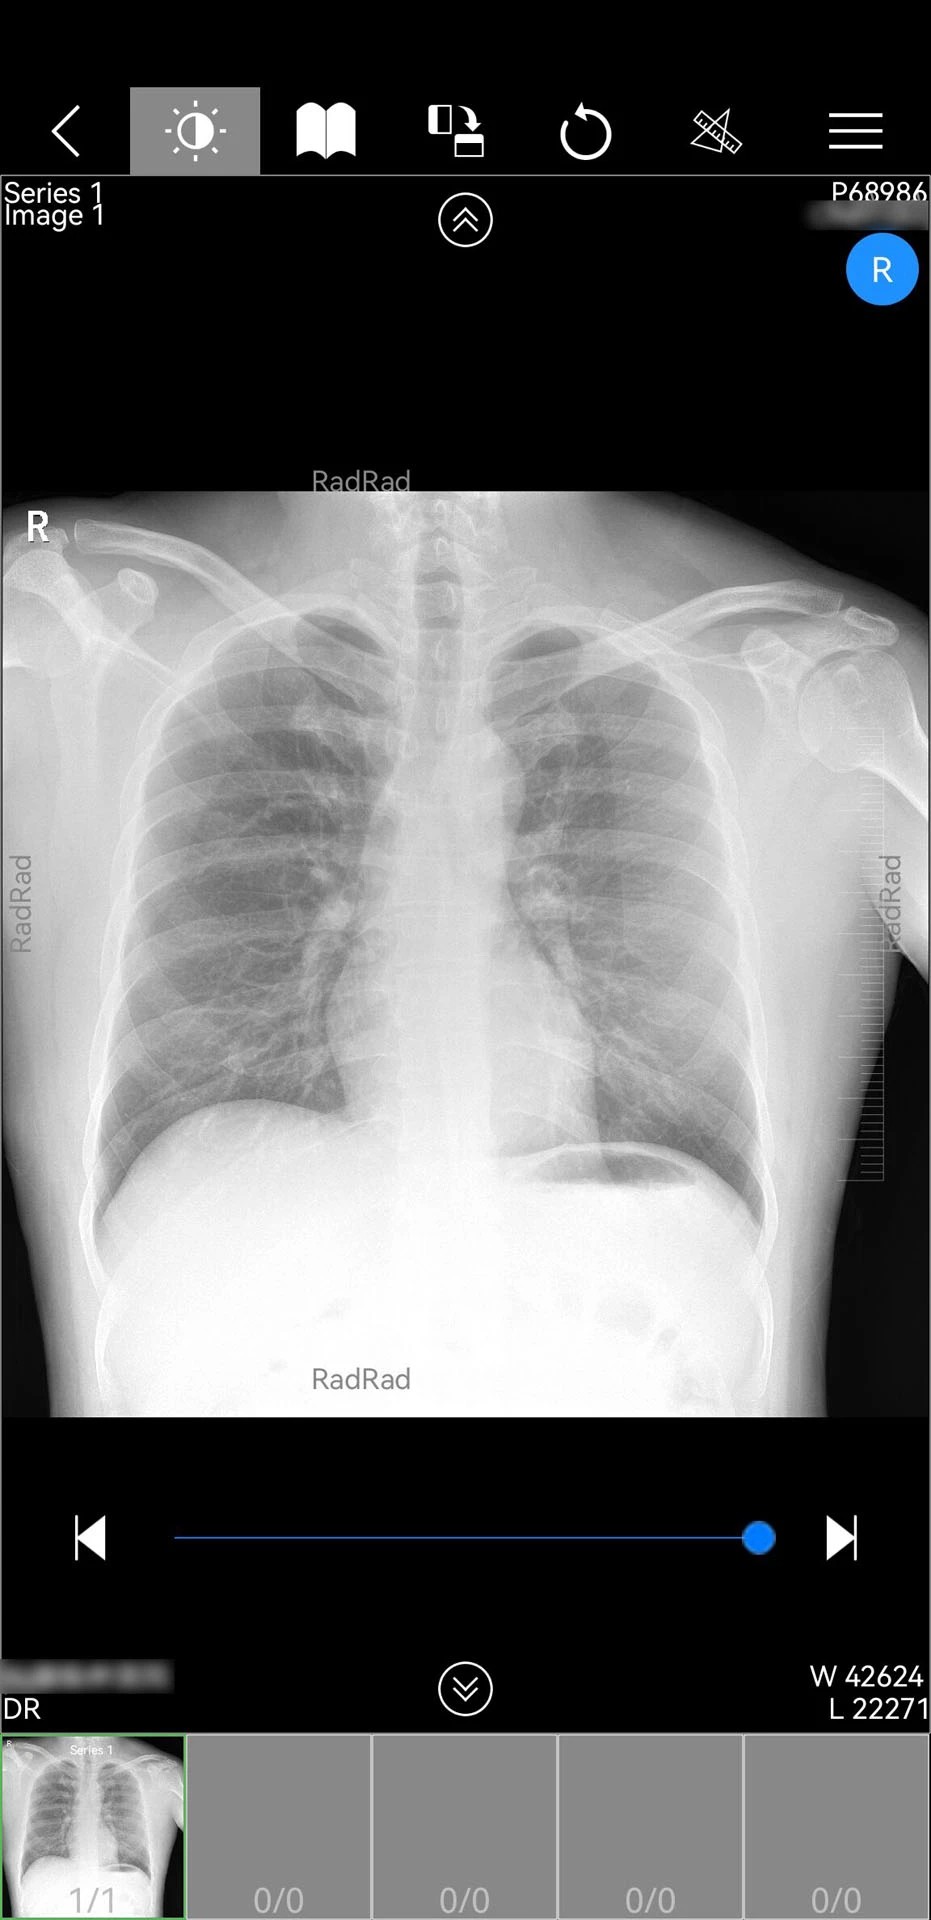

1. 全流程影像处理能力:支持DICOM格式影像的实时加载与多平面重建,医生可自由调整窗宽窗位、测量病灶尺寸,并通过三维渲染功能生成立体影像模型,辅助复杂病例分析。例如,在肺部结节诊断中,医生可通过旋转三维模型观察结节与血管的毗邻关系,提升诊断准确性。

2. 影像调阅:在“患者管理”模块输入患者ID或扫描检查单二维码,系统自动关联云服务器中的影像数据。支持按检查类型(CT、MRI、X光)或报告状态(已阅、未阅)筛选,点击影像即可进入多平面查看模式。